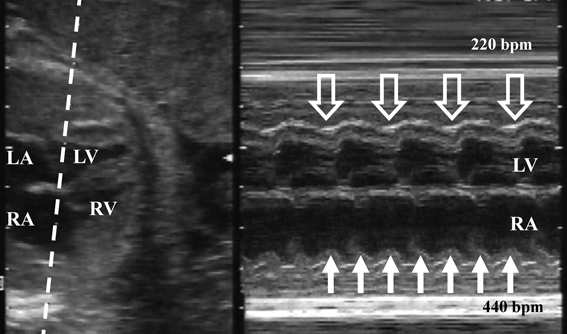

静脈の血流波形で心不全を評価する時には,心房収縮時の逆流波が増大するのを指標として使用している.しかし不整脈があると,心不全がなくても,この大きな逆流波が出現する.不整脈では,心房と心室の収縮時相にずれが生じるため,心室が収縮し房室弁が閉鎖しているタイミングで心房が収縮することがある.このとき心房収縮による血流は心室に入ることができず,静脈に向かって大きく逆流する(Fig. 4, 5).

Pediatric Cardiology and Cardiac Surgery 35(4): 221-227 (2019)

Fig. 5 Simultaneous record of the superior vena cava (SVC) and the ascending aorta (aAo) in a fetus with short VA supraventricular tachycardia

SVC flow reveals large reversal flow (arrow) made by the atrial contraction started at a line A, since the atria contracts during aAo flow which represents the ventricular systolic phase started at a line V.